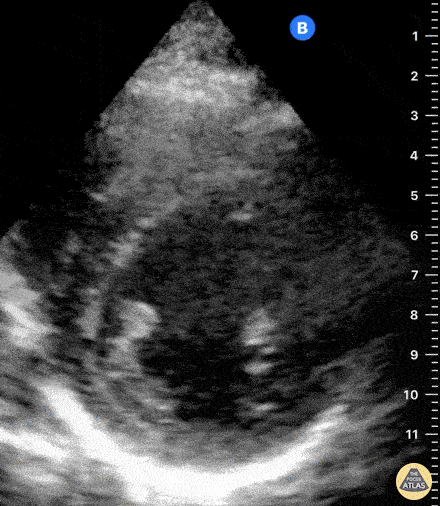

Shown above is the right hemidiaphragm or right upper quadrant view. We can see the liver and lung with the diaphragm (dotted line) in between. Note that the lung looks very similar in appearance to the liver! This liver-like appearance of the lung is called ‘hepatization’.

In the image above the lung contains small, dark linear structures that are called air bronchograms. They represent air-filled bronchi.

Lung hepatization & air bronchograms

·       This patient had a combination of both lung atelectasis and pneumonia. Typically, lung tissue is not visible on ultrasound considering that it is normally filled with air. However, in the case of pneumonia, alveoli are filled with inflammatory fluid creating consolidations, while in the case of atelectasis the alveoli are collapsed rather than fluid filled. This pathologic lung tissue is now visible with ultrasound!

·       Lung consolidations change the appearance of lung tissue on ultrasound such that its echogenicity looks remarkably liver-like, termed ‘hepatization’. This can also be seen in atelectasis.

·       Air bronchograms visible on ultrasound represent air trapped within the small bronchi which are surrounded by lung tissue. Static air bronchograms are mostly seen in compression atelectasis but can also be seen in pneumonia; they are hyperechoic air-filled bronchi that do not move with respirations. Dynamic air bronchograms are pathognomonic for pneumonia; they represent air bubbles moving through fluid filled lung tissue. On ultrasound, dynamic air bronchograms look like numerous hyperechoic opacities that move with respirations.